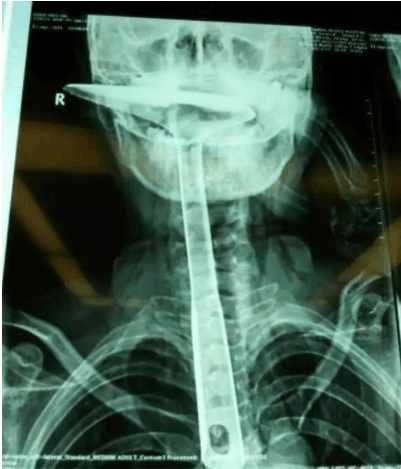

炒菜用的锅铲,长达30公分,活生生插进自己的食道,只剩下铲勺露在嘴巴外面,整个食道严重受损。医生都不禁感叹:“这真的是50年难遇的病例。”

[page]陈女士被紧急送到人民医院,医生拍片显示,整个铁锅铲把手已经在胸里了,病情严重。当晚,陈女士就被转到了康华医院。“患者来院时,嘴巴里只剩一个锅铲铲勺露在外面,整个锅铲手柄已经被插入到食道里了。”康华医院胸外科接诊医生陈羽彪说,检查发现,锅铲总长大概30公分长,手柄直径约2.5公分,整个已经插入食道,食道表皮粘膜损伤严重,且被捅破了一个洞,“而且,手柄已严重挤压到了肺部,导致右肺部已无法正常扩张。”

“这样的病例,不说100年难遇,也是50年难遇了。”康华医院胸外科主任肖朴说,患者情况严重,医院立即组织专家会诊。“胸腔全是大血管,一旦拔出就有可能大出血,危及性命。”当天晚上11点,医生决定为患者进行一期手术即食道扩置手术,“我们先将锅铲从食道里面拔出来,由于胸位食道受损严重,只能切除了。”

医生介绍,食道总长约25公分,患者切除了20公分,切除部分主要集中在胸位段,食道只保留到了颈部,只能露出来进行医学处理,吞咽口水、积液进行人工及时清理更换。”